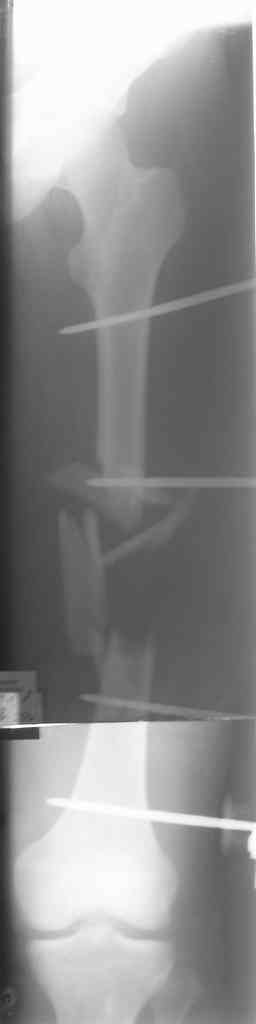

Больной 29 л 23 февраля на мопеде въехал в легковой автомобиль (естественно, больной пьяный). Поступил с диагнозом: закрытый перелом правого бедра в с/з-н/з, открытый перелом правой голени в в/з (рана в проекции перелома до 3 см), открытый оскольчатый перелом левого бедра в с/з с дефектом костной ткани (рана до 12 см по наповерхности бедра). ПО дежурству - ПХО ран, стержневые аппараты на оба бедра, аппарат Илизарова на правую голень. По стабилизации состояния - домонтаж аппарата Илизарова с окончательной репозицией. Спустя 2 недели - открытая репозиция отломков правого бедра, интрамедуллярный остеосинтез стержнем с дистальным блокированием. С правой ногой разобрались. Вопрос встает о том что делать с левой. При ревизии раны левого бедра (при поступлении) удален торчащий из раны свободный осколок до 6х3 см,загрязненный травой,пылью.Со слов скорой - на месте происшествия вроде как были еще мелкие костные осколки. Осколки что на снимке лежат по внутренней поверхности бедра, связаны с м/тканями, дефект кости до 7-8 см по длине. Массы осколков явно не хватает для его заполнения. Кроме того массивное скелетирование основных отломков (до 7-10 см в обе стороны). Все раны зажили без проблем. Наши планы - открытая репозиция левого бедра, ИМО с укорочением. Потом когда (если)срастется пусть занимаются реконструктивными операциями. Буду рад услышать ваши мнения, предложения по данному случаю.С уважением А. В. Л.

Вчера сделали снимки - положение отломков и осколков вот такое. На перевязке: из раны небольшое кол-во сгустков крови с примесью гноя , хотя бедро спокойное, гипертермии ни локальной ни общей нет. Вопрос: как быть дальше? открывать рану, "чистить" ее, наладить ее перфузию АС, АБ? что делать с осколками, попробовать перекрыть область перелома с фиксацией основных отломков аппаратом. Или осколки убрать и состыковать основные отломки с жутким укорочением и большими проблемами при зашивании раны?